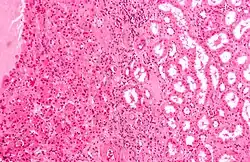

| Micrograph of a renal oncocytoma, a type of benign kidney tumour. H&E stain. | |